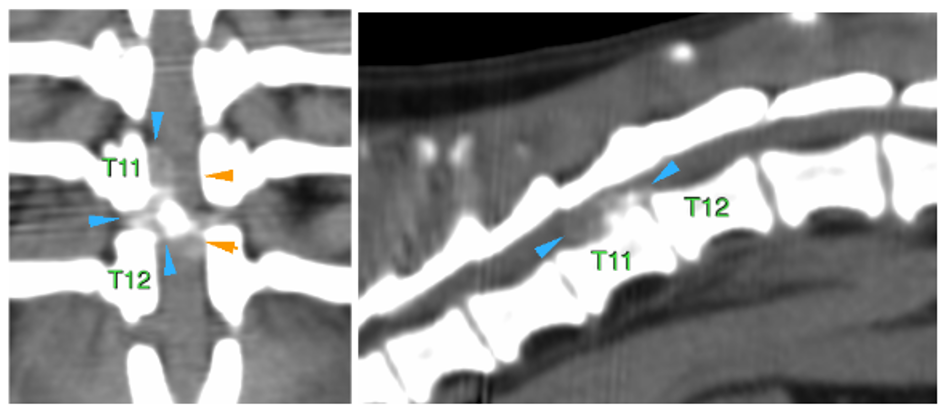

En el espacio intervertebral (IV) de T11-T12, se visualiza una lesión extradural, con presencia de material hiperatenuante (parcialmente mineralizado) localizado en el aspecto ventral del canal vertebral, lateralizado a la derecha (flechas azules).

Este material se extiende cranealmente a lo largo del cuerpo vertebral de T11 hasta su aspecto craneal, ocupando aprox. 50-70% del diámetro del canal vertebral, causando moderada/marcada compresión medular (flechas naranjas).

El material también se extiende hacia el foramen IV derecho de T11-T12.